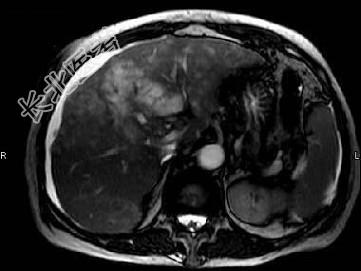

- 单项选择题根据所提供的图像,最可能的诊断是 ( )

A、胆管结石

B、肝癌

C、肝内多发囊肿

D、肝硬化

E、以上都不是